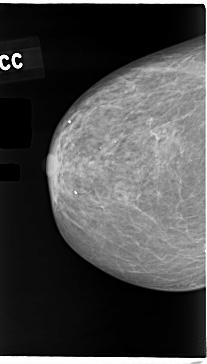

C_0049_1.RIGHT_CC

RIGHT_CC LINES 4728 PIXELS_PER_LINE 2680 BITS_PER_PIXEL 12 RESOLUTION 50 NON_OVERLAY